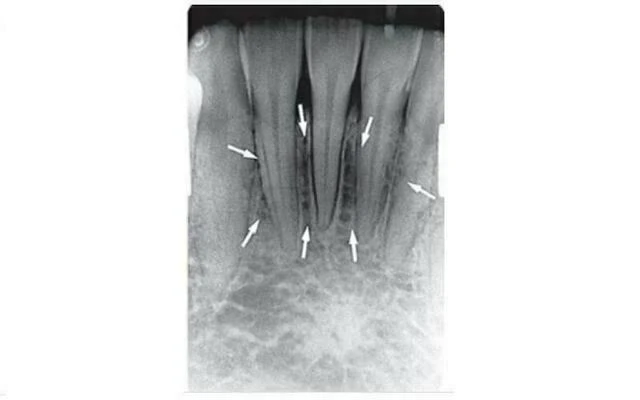

Lồi cằm

Trên phim quanh chóp răng cửa giữa hàm dưới, lồi cằm (chỗ lồi lên) đôi khi có thể thấy có hình dạng hai đường cản quang theo hai chiều hướng về phía trước và lên trên đường giữa (xem hình minh họa bên dưới). Chúng có thể có độ rộng và mật độ khác nhau và có thể mở rộng từ vùng răng cối nhỏ ở mỗi bên đến đường giữa, tại đây chúng chỉ nằm bên dưới hoặc chồng lên chân các răng cửa giữa hàm dưới. Hình ảnh lồi cằm rõ nhất khi tia được chiếu song song với bề mặt lồi cằm (như khi sử dụng kỹ thuật phân giác)